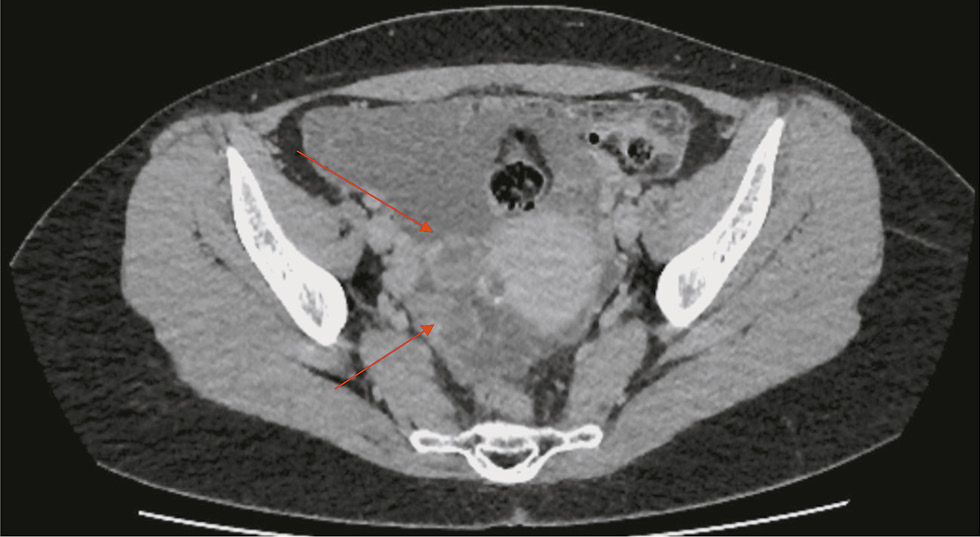

The following morning, a contrast-enhanced CT scan of the abdomen and pelvis revealed ascites and partially calcified cystic and solid formations in the right adnexal area (Fig. 1).

Fig. 1. Pelvic computed tomography (axial view). Rounded cystic and solid lesions (indicated by red arrows) and free fluid (ascites) are visible in the right ovarian area.